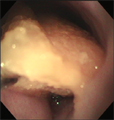

食道造影にて食道拡張が確認された。 内視鏡にて大きな食道内異物を確認した。 バスケット鉗子で部分的摘除。ササミジャーキーだった。 食道内異物完全除去後、やや陳旧性の粘膜裂傷が見つかった。

経過:T:38.8℃、P:120/分、R:60/分。南台動物病院にて食道造影にて食道拡張を認め、異物による食道炎の可能性があると診断されていた。そこで当院にて食道の内視鏡検査を行なった。まず、大きな黄白色の固い異物を確認した。バスケット鉗子で把持したが牽引時に異物の一部が切れてしまった。取り出した異物はササミジャーキーであった。はじめは食道内に残った多量の断片的なジャーキーは内視鏡観察下で大きいものからフィラリア鉗子を用いて一片づつ摘除していた。しかしジャーキー以外の異物はないことを確認したので、小さな断片を噴門前に集めスコープで送気しながら、スコープで胃内に全て押し入れた。食道内異物消失後の精査にて、ジャーキーの角が粘膜に引っかかっていたために生じたと思われる陳旧性の粘膜裂傷を1箇所見つけた。細かい断片処理に時間がかかり処置時間は全部で114分であった。食道粘膜裂傷の影響が心配されたが、次第に食道炎症状は改善し、10日後にはふやかしたフードをよく食べているとのことだった。